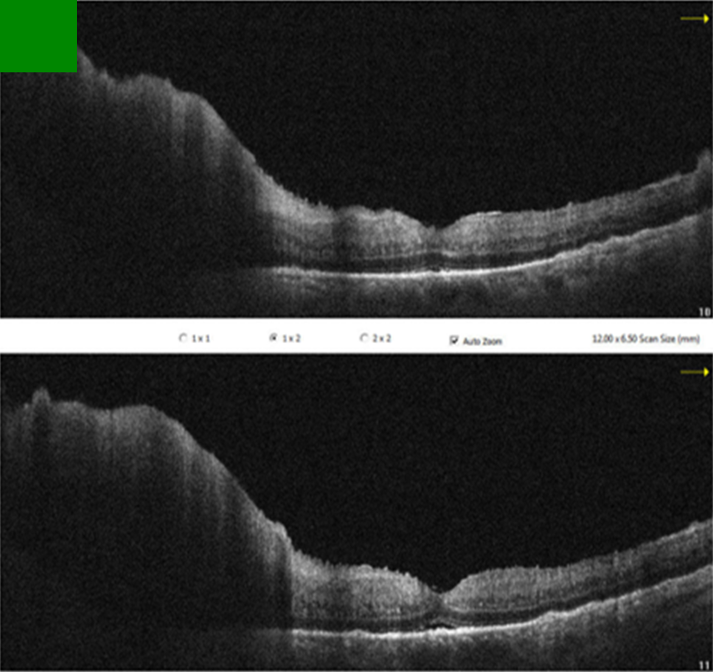

Figure 3: Pre-treatment OCT sections of the left eye

OCT revealed irregularities and multiple subretinal hyperreflective deposits at the level of the retinal pigment epithelium and Bruch’s membrane. These irregularities and deposits were predominantly observed in the left eye, accompanied by severe optic disc edema.